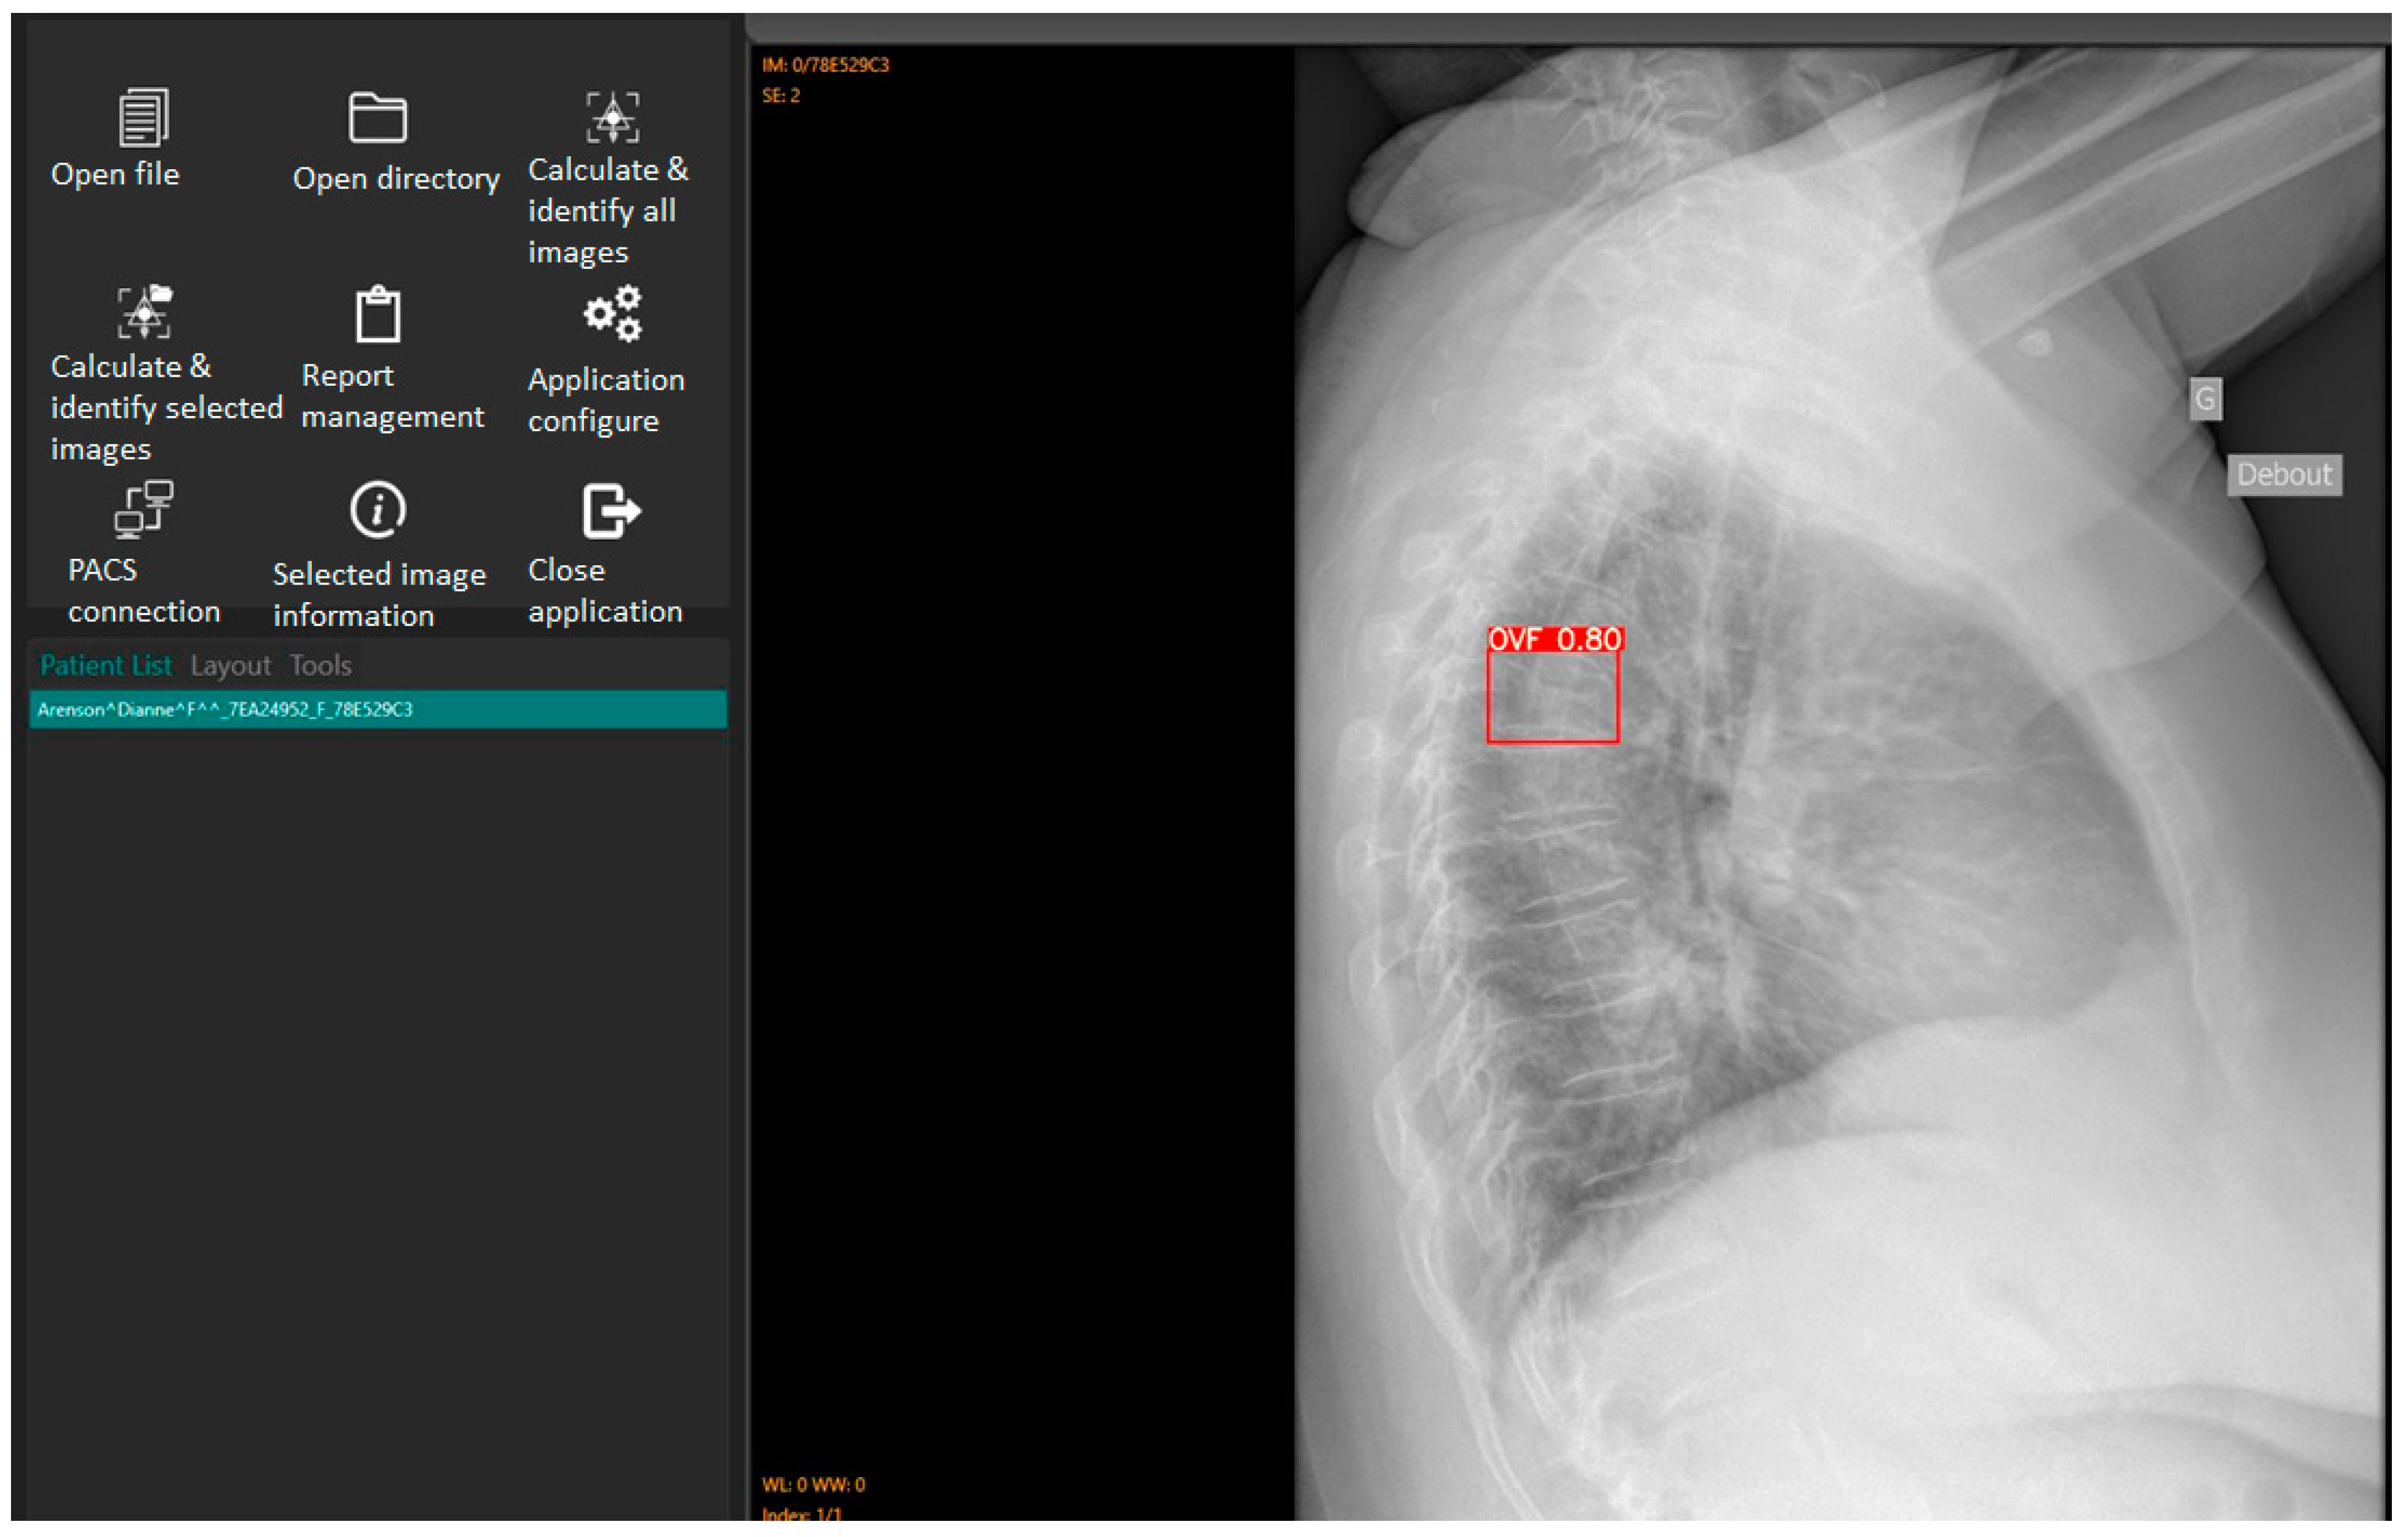

The accuracy and reliability of Ofeye 1.0 AI algorithm has been validated by Xiao et al [11]. As explained before, the primary application of this AI tool is to assist rapid and efficient identification of OVFs on chest radiographs for routine examinations and not for spinal disorders. Digital Imaging and Communication in Medicine (DICOM) images can be opened using either the “open file” or “open directory” icons. The “Calculate and identify all images” icon batch processes up to 100 images in less than 3 minutes [11], outputting a red box around identified OVFs with a percentage indicating the likelihood of a true fracture (Figure 2). Ofeye1.0 only displays an identified fracture if the percentage likelihood is at least 60% [11]..

Figure 2. Interface of Ofeye1.0 AI tool showing the steps from loading DICOM images to calculate and identify OVF on the lateral chest radiographs. In this case thee is a likelihood of 80% risk of having a fracture.